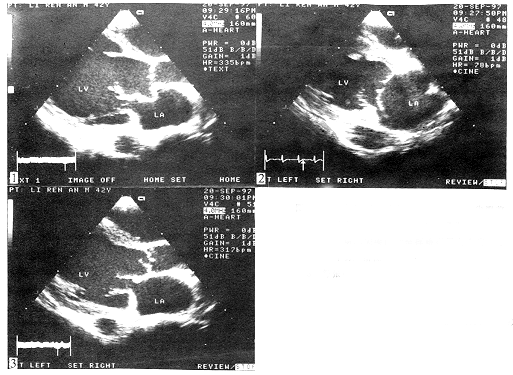

超声心动图诊断二尖瓣前叶腱索断裂 伴连枷主动脉瓣一例报告 患者, 男, 42岁。 因活动后心慌、 胸闷一年余, 腹胀四个月于1997年9月15日入院。 患者一年前因右足拇趾感染后持续高烧一个月, 临床诊断为“败血症”, 此后感心慌、 胸闷。 否认有关节疼痛史。 入院查体: 重病容, 贫血貌, 颈静脉怒张。 心浊音界向左下扩大, 心率75次/分, 律齐, 主动脉瓣区闻及全程杂音Ⅲ/6级以上, 心前区闻及Ⅲ/6级收缩期杂音, 第二心音弱。 肝肿大平脐, 压痛(+), 有股动脉枪击音及水冲脉。 临床拟诊: ①风湿性心脏病: 二尖瓣狭窄合并二尖瓣关闭不全; 主动脉瓣关闭不全。 ②感染性心内膜炎。 ③全心功能Ⅱ级。 超声心动图发现: 全心增大, 以左房、 左室增大尤著(LAs 51 mm,LVd 77 mm, RVd 26 mm, RA长径61 mm, PA 26 mm, AO 28 mm), 室间隔活动幅度增加。 左室长轴观显示二尖瓣增厚、 粗糙, 心动周期中可见二尖瓣前叶在瓣环附着处周围呈“挥鞭样”运动, 收缩期前叶冲入左房, 与后叶明显错位, 可见连接于二尖瓣前叶的腱索残端随瓣叶在心腔内漂浮。 主动脉瓣增厚, 舒张期无冠瓣甩向左室流出道, 收缩期呈180°返回主动脉腔, 无冠瓣瓣尖上有蓬草样回声漂动。 CDFI: 二尖瓣和主动脉瓣均测及重度返流信号。 超声心动图诊断: ①二尖瓣前叶腱索断裂, 二尖瓣关闭不全(重度); ②连枷样主动脉瓣伴赘生物(无冠瓣), 主动脉瓣关闭不全(重度); ③全心功能不全(图1~3)。

图1 左室长轴观显示左心显著增大, 二尖瓣前叶腱索残端随瓣叶在心腔内漂动

图2 收缩期二尖瓣前叶呈挥鞭样甩向左房, 与后叶明显错位

图3 舒张期主动脉瓣无冠瓣甩向左室流出道